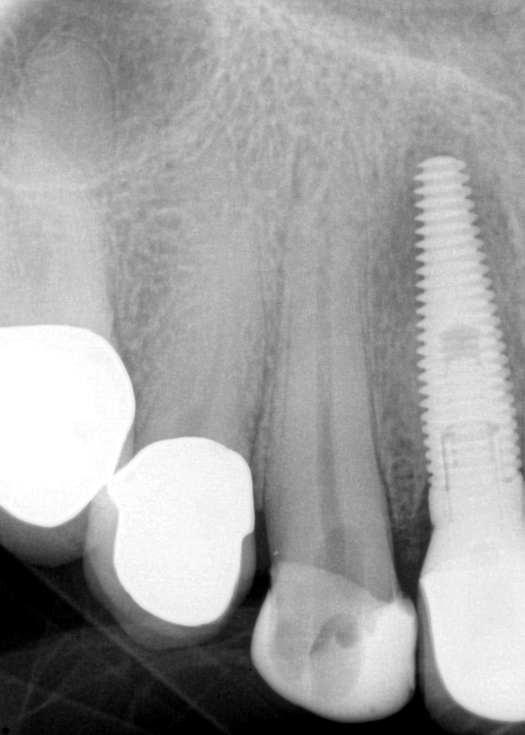

Fig 7. Primary endodontic and secondary periodontal lesion, mandibular second molar.

Figure 7

In Figure 7, the periapical radiograph identifies the presence of the combined endodontic-periodontal lesion developing due to a carious lesion beneath an existing vintage gold crown with ill-fitting margins. Intraoral examination revealed a fistula developing and moderate pain on percussion and mastication. After occlusal access and clear visualization of the canals, the canals were shaped using the rotary files, with precautions taken not to perforate or enlarge the apical foramen. Maintaining the endodontic therapy within the canals prevents the infection from being introduced into the surrounding periodontium. In this case, calcium hydroxide medicament was placed into the canals and evaluated 30 days postoperatively.8

The patient returned for final evaluation of the provisional calcium-hydroxide endodontic therapy and resolution of the infection (33 days postoperatively). Fistula was not present; the tooth was not sensitive to percussion or mastication. The gold crown was removed using a high-speed metal cutting bur, the remaining caries were excavated conservatively, and the endodontic therapy was completed. Placement of glass-fiber reinforced composite and composite core buildup took place. The natural tooth structure to receive the glass-fiber post and a long-term restoration was available (Figure 8). Within one appointment, the tooth was restored (Figure 9). The patient was instructed to return for clinical and radiographic evaluation after 6 to 12 months to determine progression of periodontal healing. At that time, if the healing were adequate and the tooth were stable, evaluation of the tooth would be considered every 3 to 4 years.7